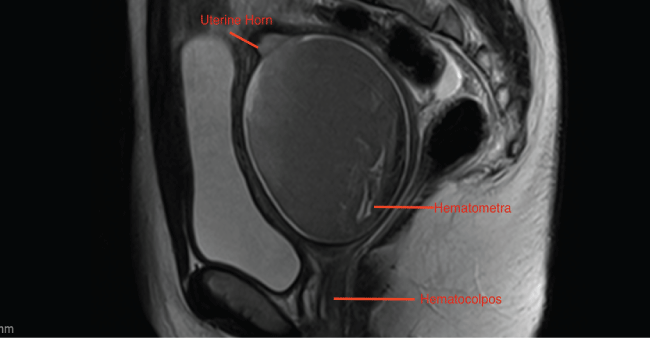

Abdominal ultrasound confirmed absent left kidney. Transabdominal pelvic sonogram revealed two prominent uterine cornua with an endometrial thickness of 3 mm in each horn. The right cornu measured 11.4 × 2.0 × 3.6 cm and the left cornu measured 10.4 × 2.8 × 4.1 cm. A 7 cm mass in the endocervical canal, concerning for hematocolpos, represented an occlusion extending to the left vagina (Figure 1).

She underwent further imaging with two MRI studies that were mutually inconclusive and inconsistent in regards to her pelvic anatomy. An intravenous pyelogram demonstrated a solitary right kidney with a normal right renal collecting system and a single ureter extending toward the bladder.

Postoperative imaging with MRI demonstrated two uterine horns with collapsed endometrial cavities and resolution of hematocolpos. Bleeding occurred through a single midline cervical os.